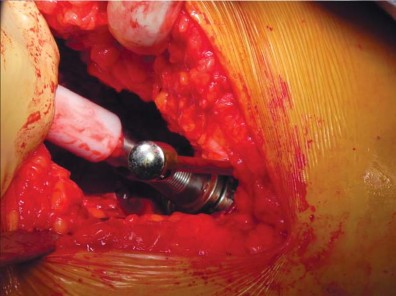

التقنية الجراحية للدكتور محمد هطيف

يستخدم الأستاذ الدكتور محمد هطيف تعديلًا طفيف التوغل للطريقة الجانبية المباشرة (LIDL) لضمان أفضل النتائج لمرضاه. هذه التقنية تضمن دقة عالية مع الحفاظ على الأنسجة.

وضعية المريض والشق الجراحي

يتم وضع المريض في وضع الاستلقاء الجانبي المباشر مع الجانب المراد إجراء الجراحة عليه للأعلى، والحوض عموديًا على الطاولة باستخدام دعامة صلبة. لضمان الاستقرار، يتم وضع دعامات طويلة خلفيًا عند مستوى منتصف الظهر وعند منتصف العجز، وأماميًا عند عظم القص والارتفاق العاني. يتم ثني الورك المقابل حوالي 15 درجة ويتم تبطين الشظية القريبة لمنع الضغط الزائد على العصب الشظوي المشترك. في هذا الوضع، يتم تقدير تقريبي لتساوي طول الساقين عن طريق تقييم مستوى الرضفتين والكعبين. بعد التحضير والتعقيم، يتم تحديد طرف المدور الكبير عن طريق الجس والتقييم عن طريق الجلد باستخدام إبرة نخاع شوكي.

يتم عمل شق مائل من الخلف القريب إلى الأمام البعيد، يتمركز فوق طرف المدور الكبير، ويبلغ طوله حوالي 10-12 سم للرجل متوسط الوزن (70 كجم). يتم تقليل تشريح تحت الجلد لتحديد اللفافة الأساسية إلى الحد الأدنى لمنع تكوين مساحة ميتة.

إدارة الأنسجة الرخوة وخلع رأس الفخذ

تُشق اللفافة العريضة والألياف الأمامية للعضلة الألوية الكبرى التي تتصل باللفافة العريضة قريبًا باستخدام الكي الكهربائي بما يتماشى مع شق الجلد. يتم إزاحة الجراب المدوري خلفيًا للمساعدة في رؤية العضلة الألوية الوسطى والعضلة المتسعة الجانبية. يتم رفع الجزء الأمامي من العضلة الألوية الوسطى عن المدور الكبير باستخدام الكي الكهربائي، ثم يتم تشريحه بشكل غير حاد بما يتماشى مع أليافه بزاوية 45 درجة أمامية-قريبة عند تقاطع الثلثين الأوسط والأمامي للعضلة. يقتصر التشريح على أقل من 3-4 سم باتجاه الرأس من طرف المدور الكبير لتجنب إصابة العصب الألوي العلوي. في غلاف مستمر مع العضلة الألوية الوسطى، يتم رفع الجزء الأمامي من العضلة المتسعة الجانبية عن حافة العضلة المتسعة ويتم شقه بعيدًا بين ثلثيه الأوسط والأمامي. يتم وضع مبعد هومان غير حاد في شق العضلة الألوية الوسطى لسحب الألياف الخلفية وكشف طبقة من الدهون بين المستويات الألوية. تُشق الكبسولة خلف العضلة الألوية الصغرى وعلى طول الجانب العلوي من عنق الفخذ. يقوم المساعد بتباعد وثني وتدوير الطرف خارجيًا لخلع رأس الفخذ.

تحضير الفخذ والحق

يتم تحديد مستوى قطع عنق الفخذ مسبقًا بالتخطيط (باستخدام الأشعة السينية) ومواءمته أثناء الجراحة مع المدور الكبير. بعد قطع عنق الفخذ، يتم تحضير الحُق بالطريقة القياسية قبل تحضير الفخذ. يفضل الأستاذ الدكتور محمد هطيف عادةً وضع الكأس وفقًا للمعالم التشريحية لإعادة إنشاء التوجيه الطبيعي للحُق لدى المريض ويتحقق من الإصدار والميل الصحيحين عن طريق الجس والرؤية المباش